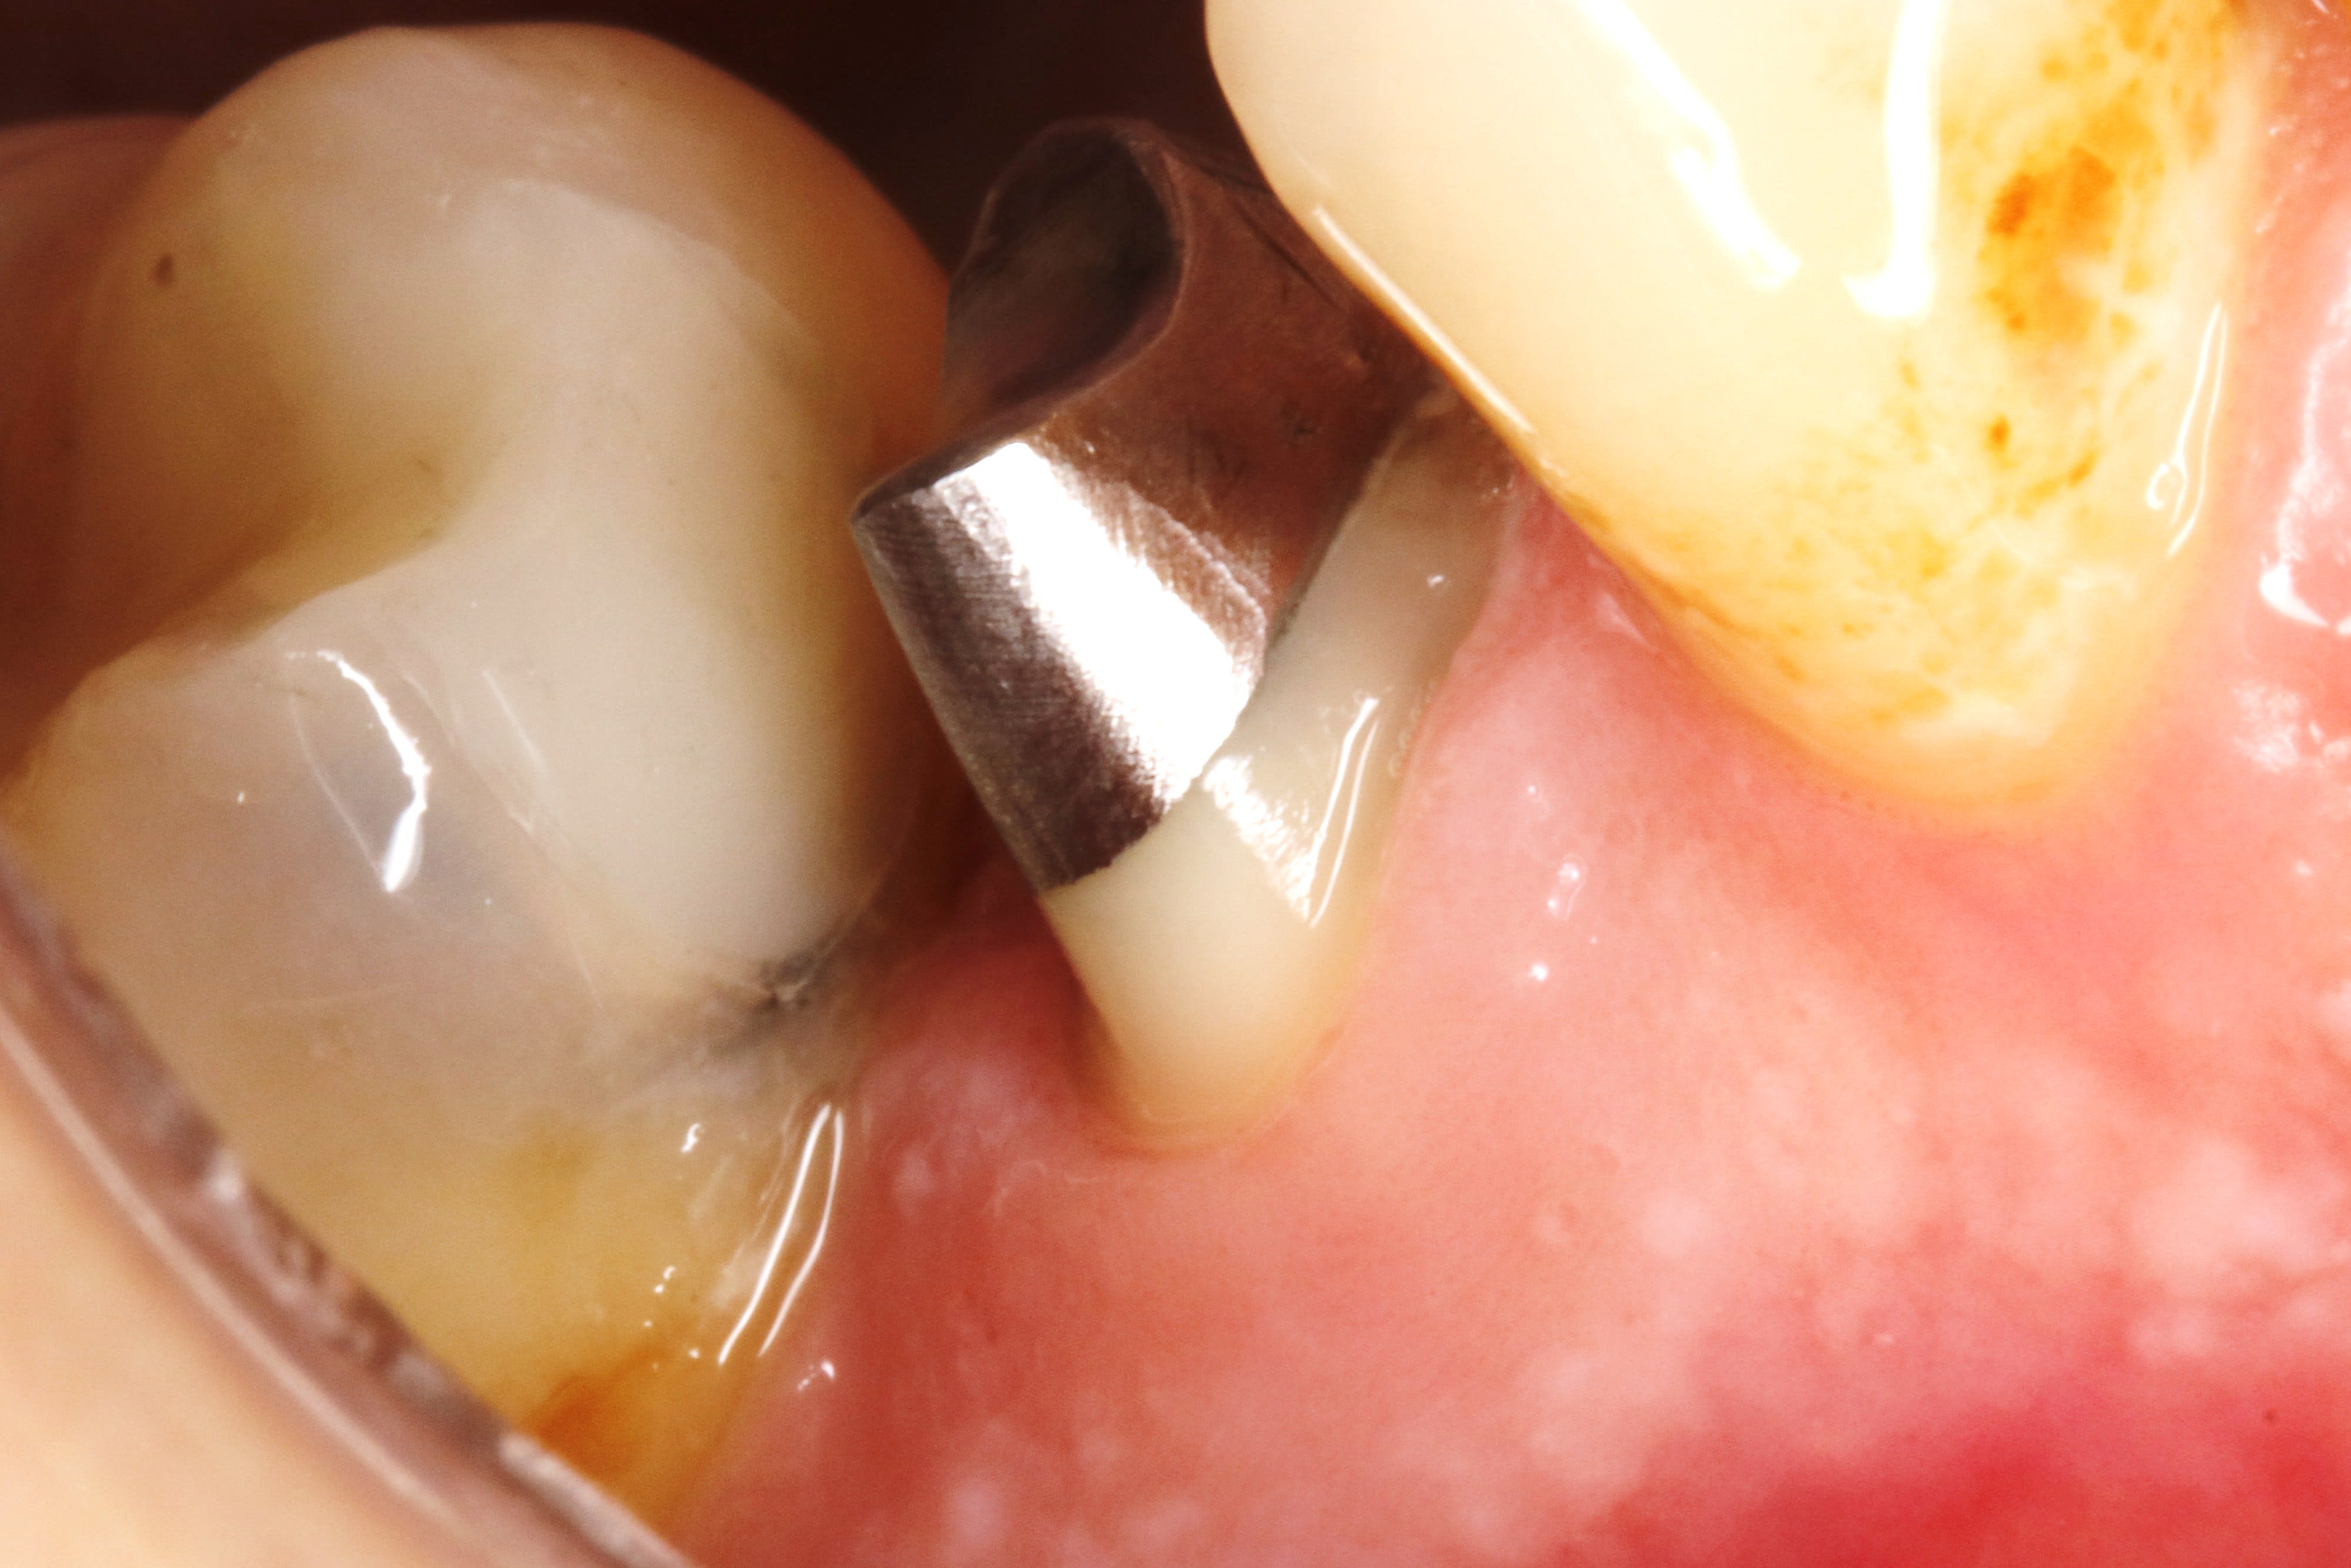

voilà , ce matin on est donc à 1 semaine .

on voit que la gencive ç est tassée .

je dis tasseé pcq on ne peut pas dire cicatrisée puisqu on ne l avait pas touché la semaine passée .

on peut mettre 1 fil , et meme se servir du chausse pied , ça ne saignera pas , ç est du beurre .

et on reprecise les limites à la grain fin .